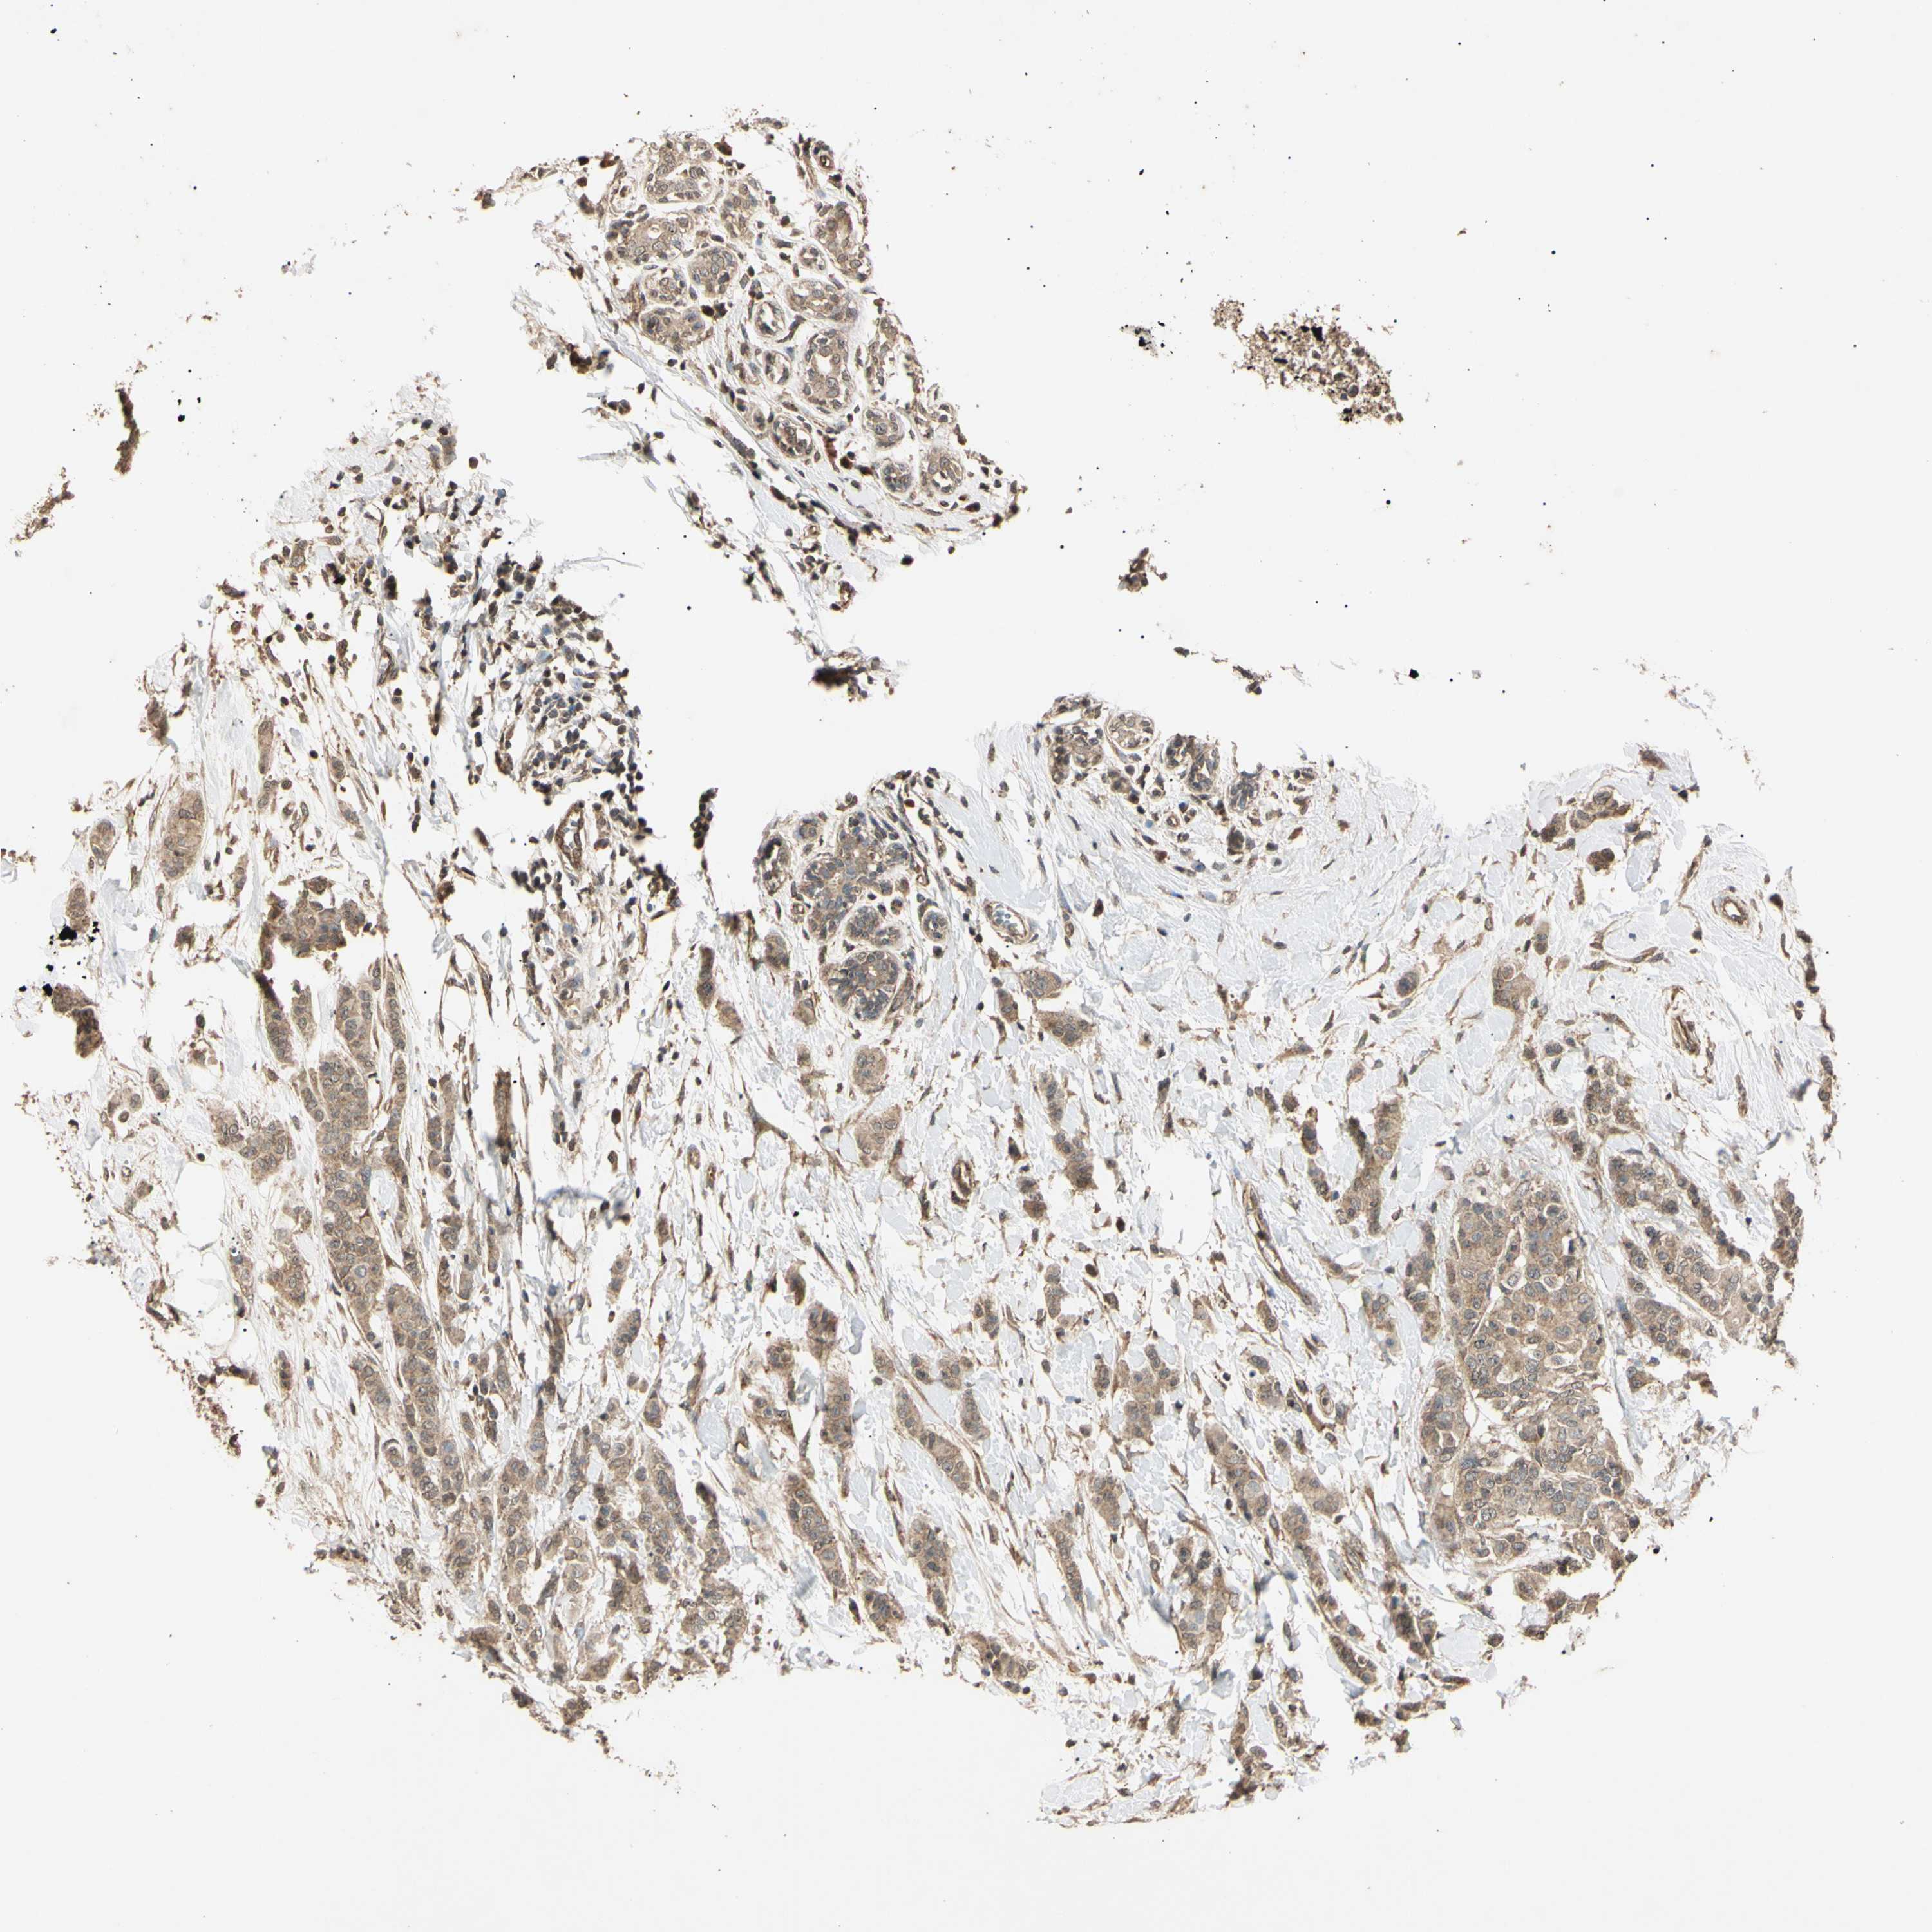

CANCER BREAST CANCER Show tissue menu

BRCA TCGA BRCA VALIDATION PROTEIN EXPRESSION